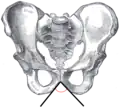

![]() Female pelvis (pubic arch labeled at bottom center) | |

The pubic arch, also referred to as the ischiopubic arch, is part of the pelvis. It is formed by the convergence of the inferior rami of the ischium and pubis on either side, below the pubic symphysis. The angle at which they converge is known as the subpubic angle.[1]

The pubic arch is one of three notches (the one in front) that separate the eminences of the lower circumference of the true pelvis.

The subpubic angle (or pubic angle) is the angle in the human body as the apex of the pubic arch, formed by the convergence of the inferior rami of the ischium and pubis on either side. The subpubic angle is important in forensic anthropology, in determining the sex of someone from skeletal remains. A subpubic angle of 50–82 degrees indicates a male; an angle of 90 degrees indicates a female.[2] Other sources operate with 50–60 degrees for males and 70–90 degrees in females.[1] Women have wider hips, and thus a greater subpubic angle, in order to allow for child birth.

Female subpubic angle